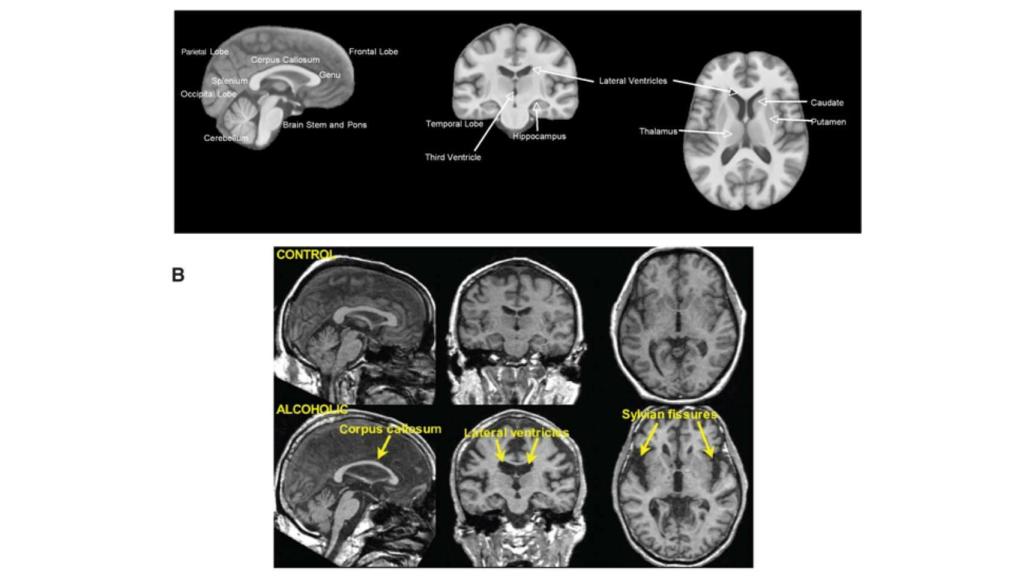

Daños en las regiones del cerebro provocados por el alcoholismo. Niaaa.nih.gov